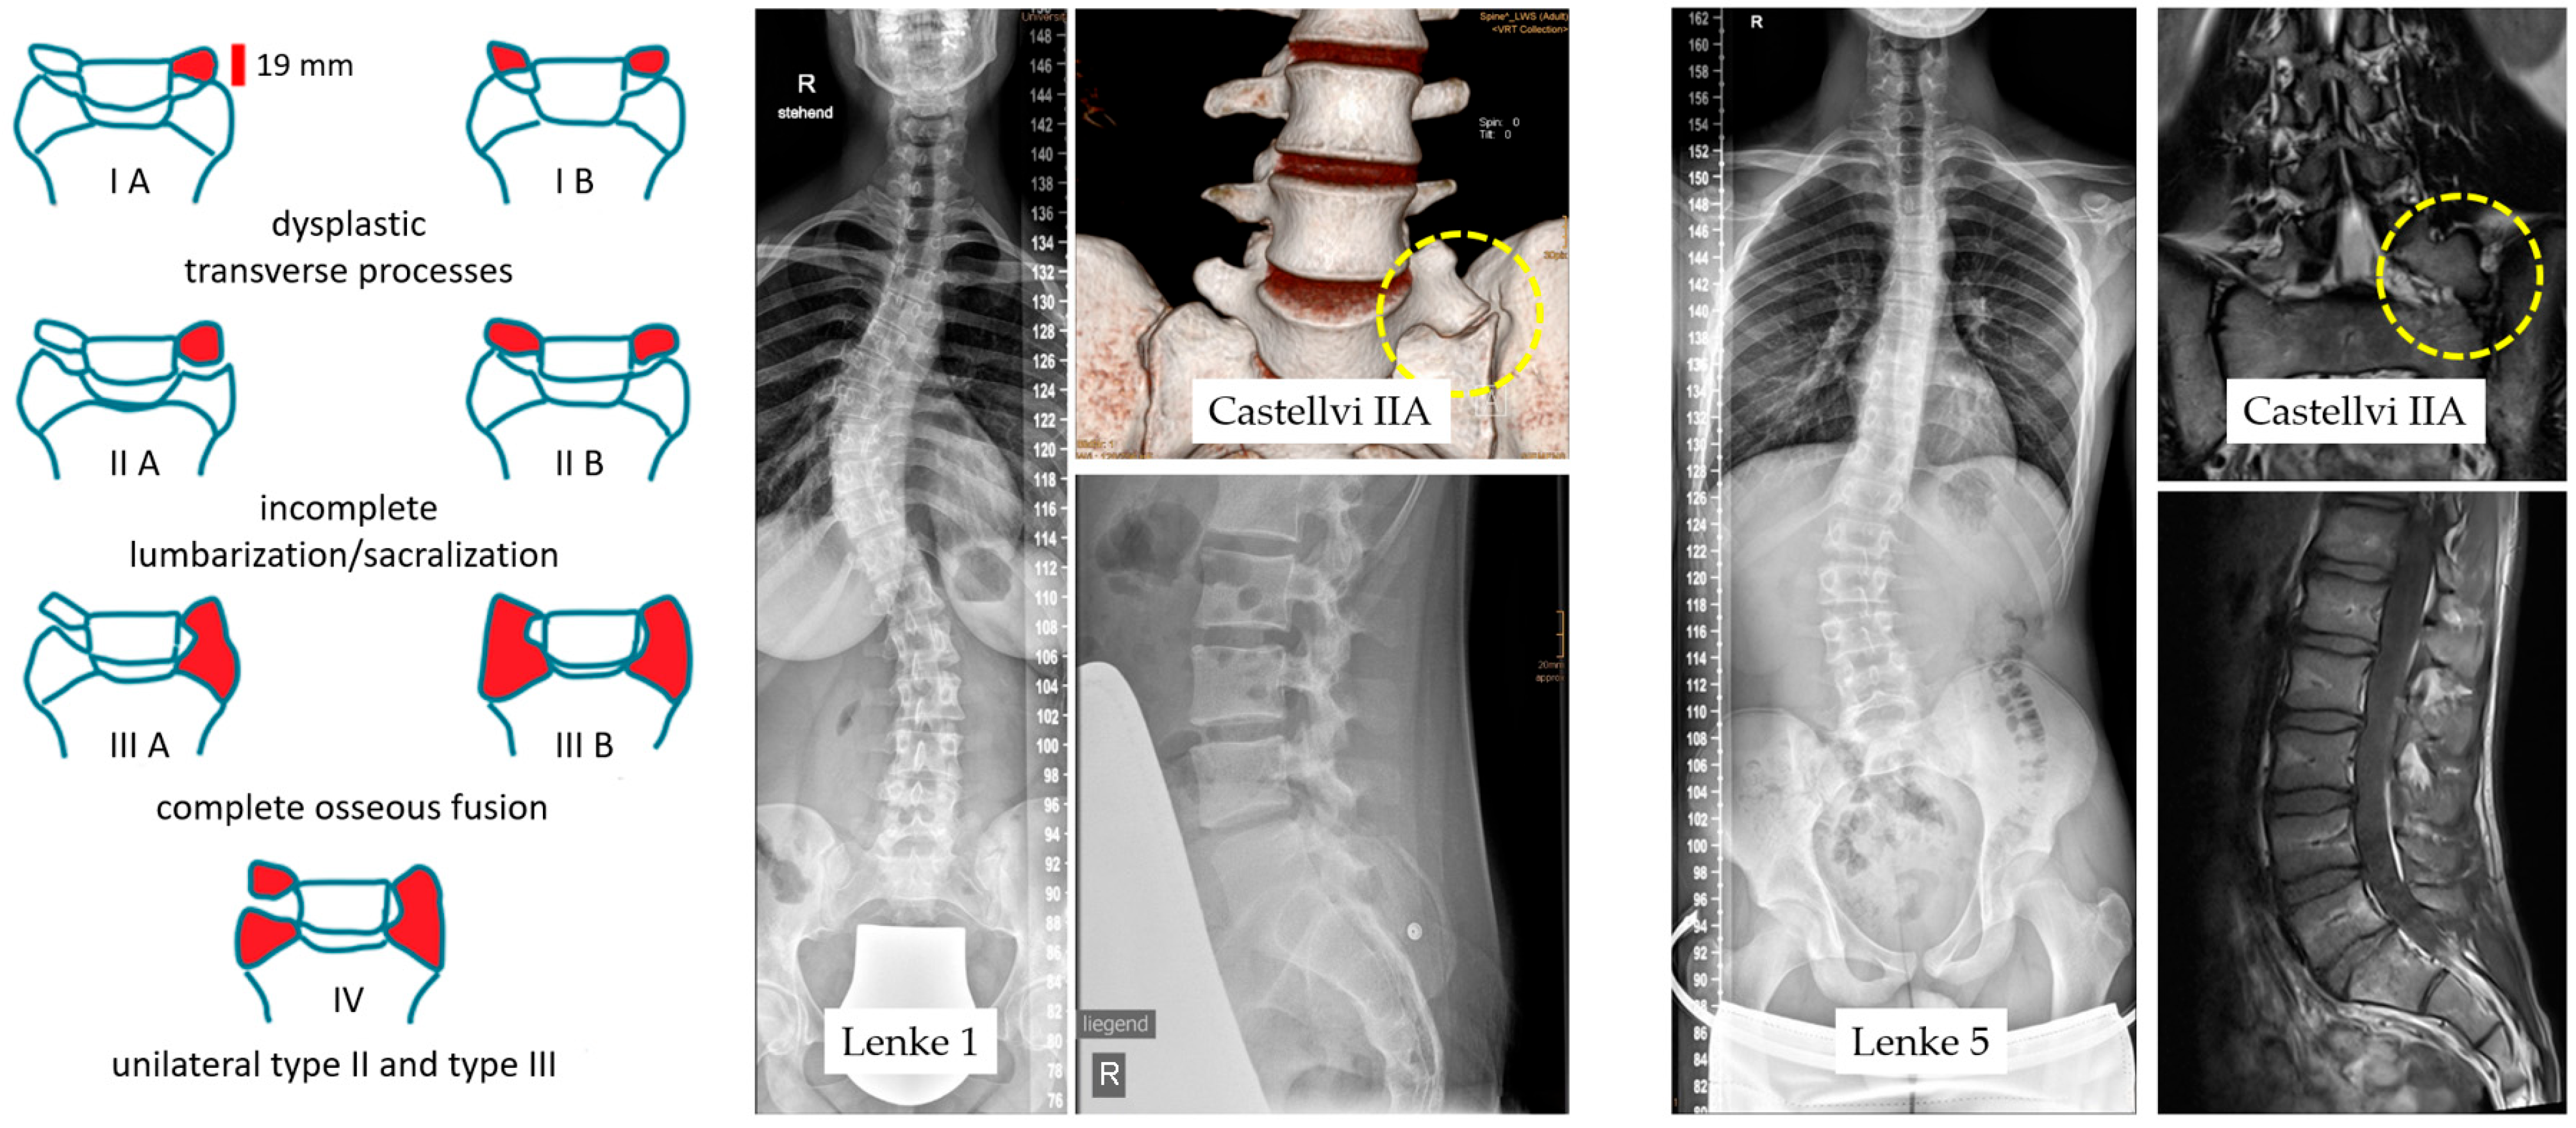

3.1. LSTVs in Castellvi Classification

3.3. Curvature Shape in the Lenke Classification

| Castellvi Classification | Total Data | Male | Female | |||

|---|---|---|---|---|---|---|

| n-72 | 19.4% | n-14 | 80.6% | n-58 | ||

| IIA | 54.2% | n-39 | 11.1% | n-8 | 43.1% | n-31 |

| IIB | 20.8% | n-15 | 5.6% | n-4 | 15.3% | n-11 |

| IIIA | 12.5% | n-9 | 1.4% | n-1 | 11.1% | n-8 |

| IIIB | 9.7% | n-7 | 1.4% | n-1 | 8.3% | n-6 |

| IV | 2.8% | n-2 | 2.8% | n-2 | ||

| Lenke | lumbar Spine Modifier | Chronic Low Back Pain | |||||

|---|---|---|---|---|---|---|---|

| A | B | C | |||||

| 1 | 25.0% | n-18 | n-7 | n-7 | n-4 | 9.7% | n-7 |

| 2 | 4.2% | n-3 | |||||

| 3 | 4.2% | n-3 | |||||

| 4 | 1.4% | n-1 | |||||

| 5 | 62.5% | n-45 | n-10 | n-13 | n-22 | 32.9% | n-23 |

| 6 | 2.8% | n-2 | |||||